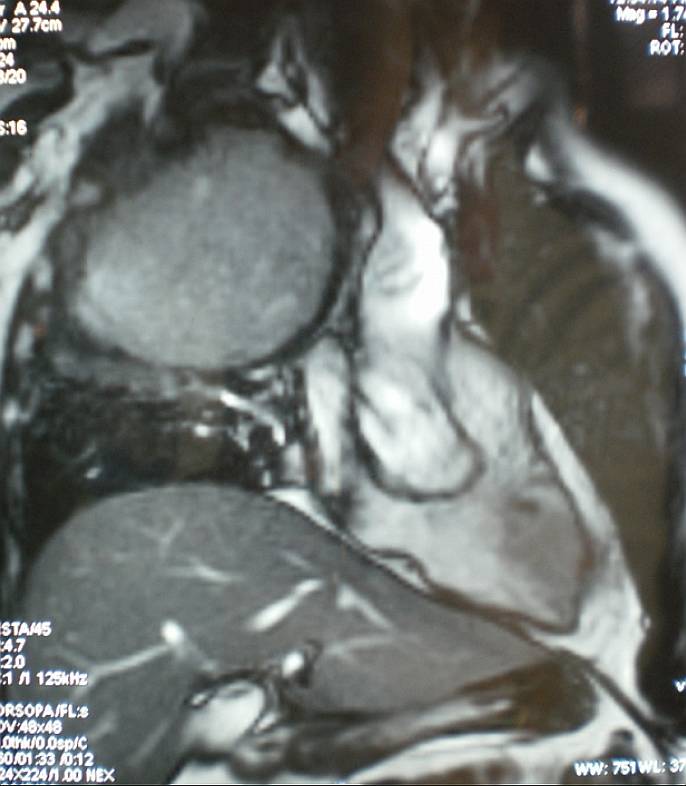

MRI provided superior demonstration. T1- and T2-wighted images showed a well-circumscribed mass without evidence of spiculation or satellite nodules. A peripheral rim of enhancement in the lesion was demonstrated after the administration of gadolinium.